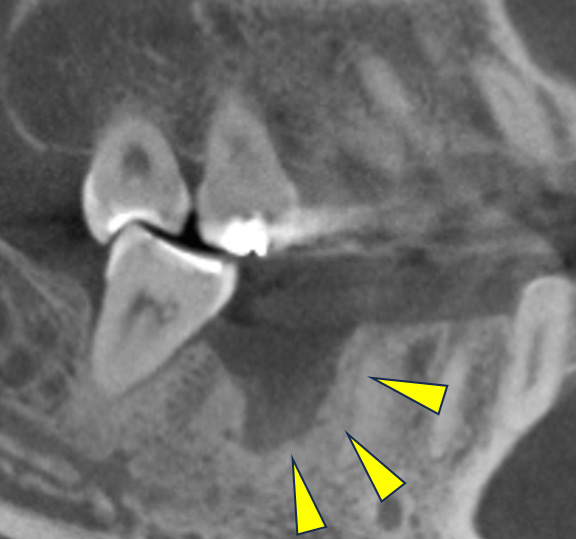

親抜歯後、歯ぐきは治癒しました。しかし、インプラント治療のためには骨が不足していました。

CT画像 -

骨移植(人工骨+メッシュプレート)を行い、骨を造りました。